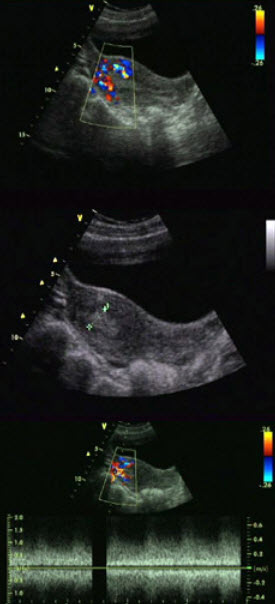

女,24岁,人流术一月后阴道不规则出血。根据超声所示,应考虑为()

A.宫内残留

女性,27岁,上环3月,月经量多,超声检查见图,最可能的诊断是()

A.宫颈炎

图中为一称曼月乐的节育器,其纵管内含有一种激素类药物,释放出此药后达到避孕效果.此激素为()

A.孕激素